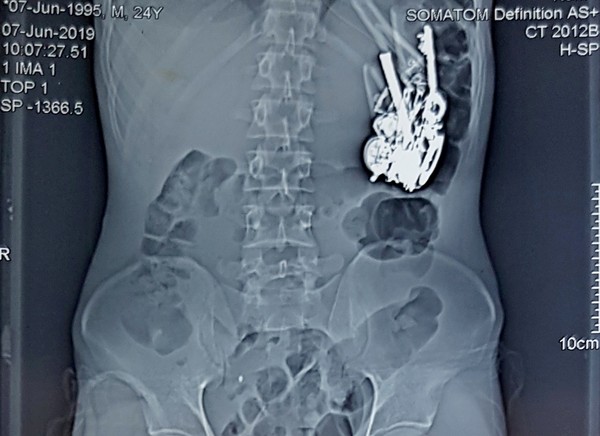

24岁男腹痛就医!胃竟堆满刀片、钥匙、指甲剪「80种异物」!医生傻眼!

印度拉贾斯坦邦(Rajasthan)乌代浦(Udaipur)有一名24岁青年日前因为腹痛、长期慢性呕吐就医,结果医生帮他进行腹部、肠道扫描后,发现他的腹中内竟有80多种金属及其他材质异物,吓得立刻进行手术将异物全部取出。他事后也告诉医生,自己只要精神抑郁,就会想吞食异物。

综合媒体报导,当地医院的外科医生夏尔马(Dr Sharma)表示,病患就医时自称有长期慢性呕吐、腹痛、食欲不振等症状,因此他就替对方进行腹部、肠道的电脑断层扫描及X光扫描,结果就发现病患的胃部积了一堆的异物,手术后进一步发现是80多种金属及玻璃、木质等材质的异物。

夏尔马取出男子体内所有异物后相当傻眼,因为里头包含各种非常离奇的物品,像是硬币、吸食大麻用的短陶管、指甲剪、一些玻璃制品、钥匙、钥匙圈、项链、发夹、刀片、安全别针和眼镜领带夹,而且一些铁器外观有明显的生锈痕迹,因此男子应该已经吞食有一段时间了。

男子手术后也向医生透露,自己只要精神抑郁,就会想吞食异物,长期累积才会这么多。夏尔马指出,人体内发生如此大量的尖锐物品相当不寻常,等待对方的身体状况恢复后,他们就会对男子进行心理方面的检查及评估。